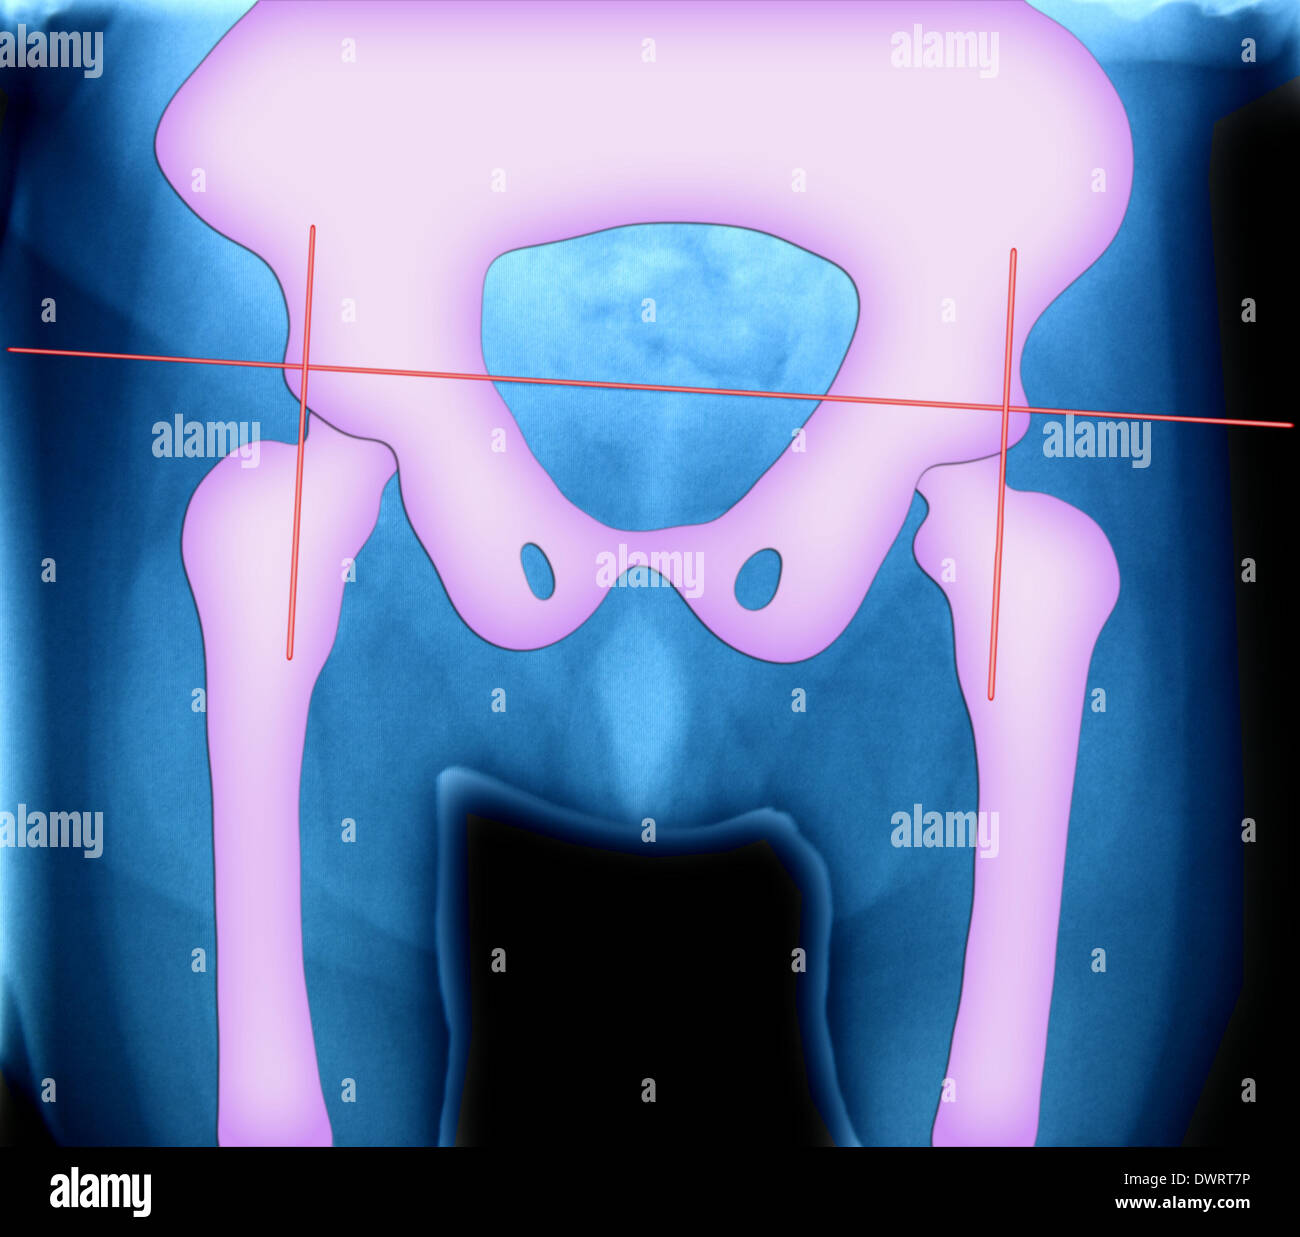

XRay of Pelvis Stock Photo Alamy Pelvis X Ray Labeled The pelvis series examines the main pelvic ring, obturator foramina, sacroiliac joints, symphysis pubis, acetabulum, sacral foramina, and the proximal femur. The innominate bones articulate with each other anteriorly and with the The pelvis radiograph is comprised of the innominate hip bones or os coxae (ischium, pubis and ilium), the sacrum and the proximal. 6.1a, b) is a bony ring. Pelvis X Ray Labeled.